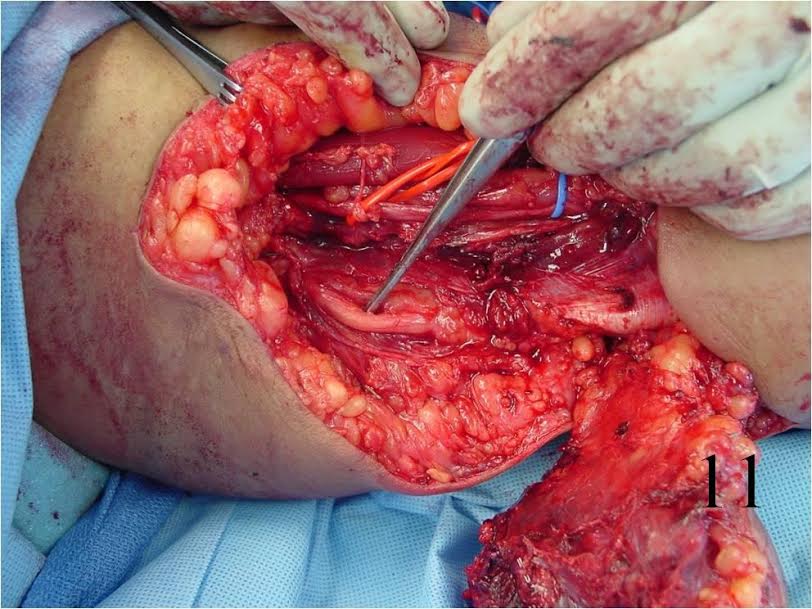

- Wide resection and postoperative radiation (Fig 10, 11)

Fig. 10, 11 Intraoperative photographs of a resection of tumor arising in upper extremity.